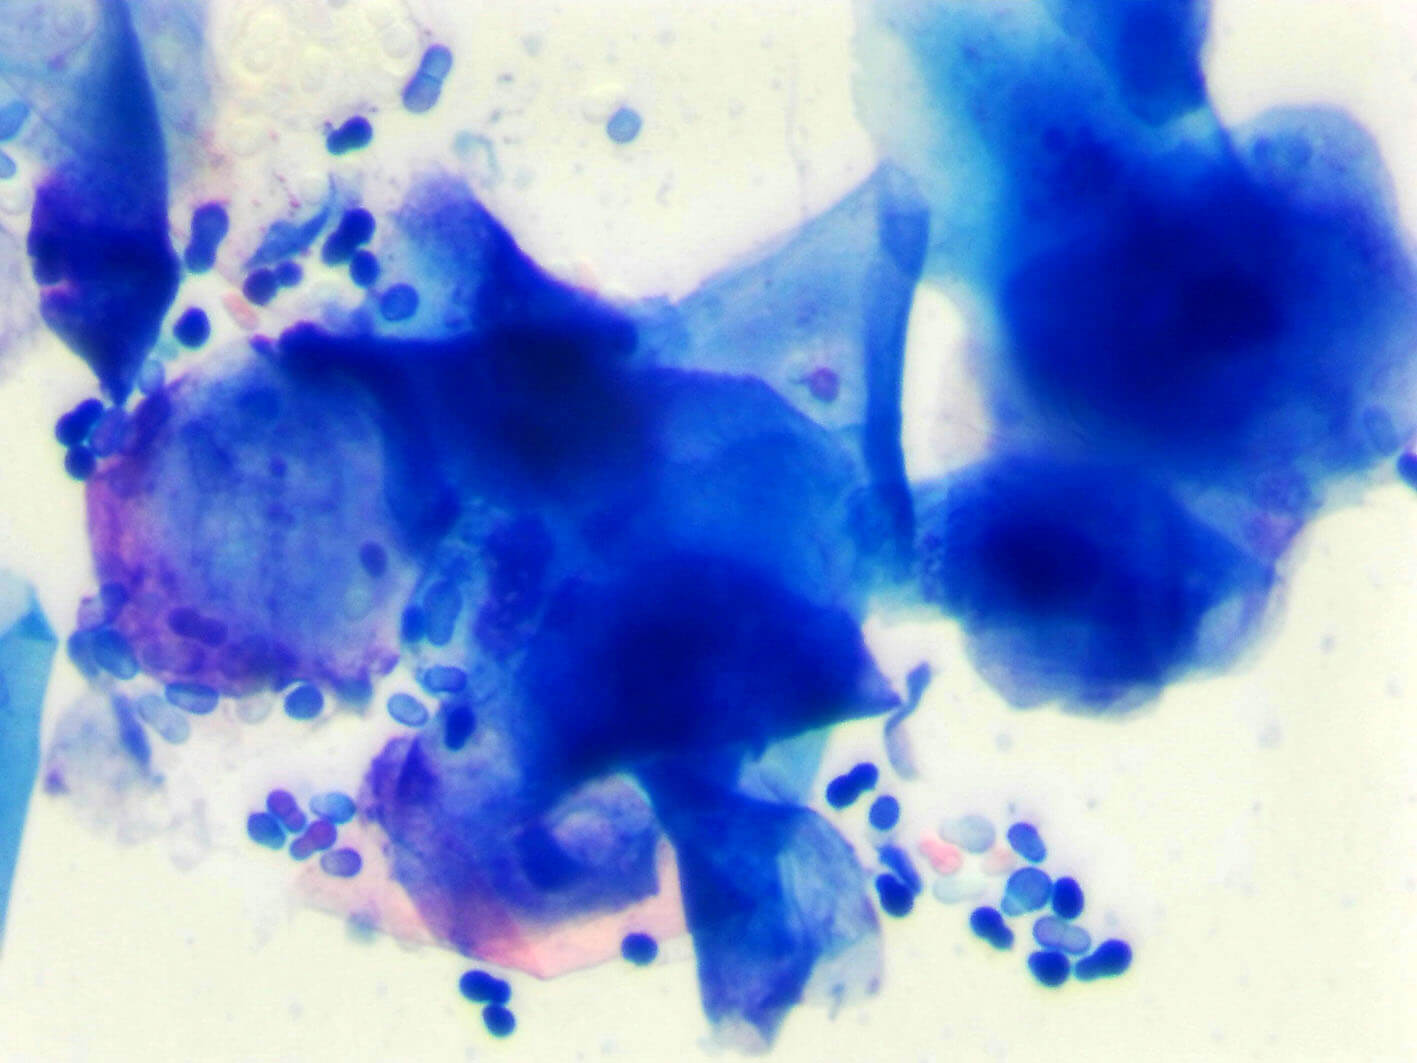

Cytologická diagnostika uší

Cytológia zvukovodu je základným vyšetrením pri každej otitíde.

Umožňuje:

identifikovať baktérie, kvasinky a zápalové bunky,

zvoliť správnu lokálnu alebo systémovú liečbu,

kontrolovať účinnosť terapie.

✔️ Cytologická diagnostika výrazne znižuje riziko neúčinnej liečby.